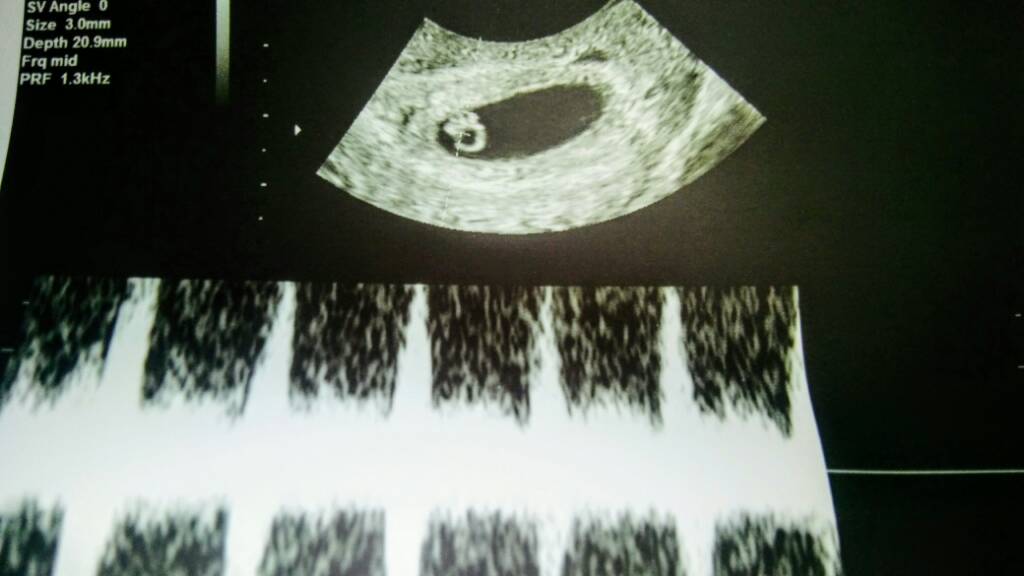

Dziekuje za wsparcie[emoji5] wrocilismy juz do domku[emoji5] wszystko jest dobrze. Ciaza rozwija sie prawidlowo i serduszko pracuje jak dzwon[emoji173] a o to moje malenstwo....[emoji175]

1484310923-aaaaaa.jpeg